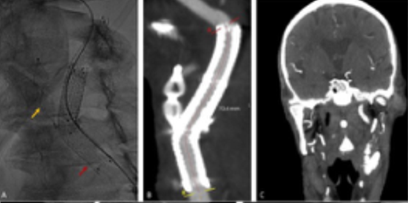

Control CTA at 24 hours revealed a "type 1 endoleak" with contrast leak filling from the proximal landing zone, Figure 3. A second procedure was performed through a transfemoral approach. An 8Fr 70cm sheath was placed at the origin of the CCA through a right percutaneous femoral access. The external carotid artery ostium was occluded with an 8mm vascular plug (Amplatzer™ Vascular Plug 4, 8x13.5), followed by stentgraft extension to the common carotid artery with an 8x50 Viabahn®, Figure 4.

Figure 3 Control computed tomography angiography showing a contrast leak (red arrows) from the proximal landing zone. A) coronal view; B) sagittal view.

The patient underwent a 21-day course of intravenous antibiotics with piperacillin-tazobactam, transitioning to oral levofloxacin upon discharge, according to the antibiogram. The antibiotic therapy was suspended by the 9th week after a multidisciplinary discussion with the infectiology team, with sustained negative blood cultures and complete resolution of symptoms, Figure 4.

Figure 4 Post-operative imaging after external carotid artery (ECA) occlusion with a plug with an 8mm vascular plug stentgraft extension to the common carotid artery. A) Intraoperative image showing Amplatzer™ Vascular Plug 4, 8x13.5 (yellow arrow) and 8x50 Viabahn® (red arrow); B) computed tomography angiography at 24h showing ECA occlusion and patent stents with resolution of the leak; C) computed tomography angiography at one month significant reduction of the cervical hematoma (coronal view).